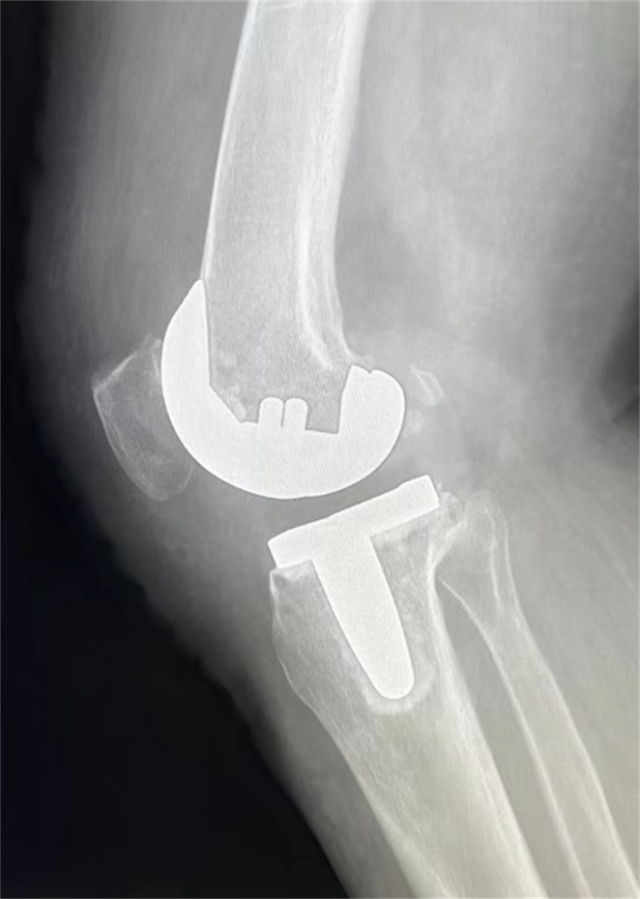

患者术后影像资料